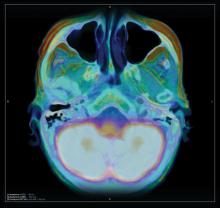

Advanced imaging and hybrid modalities, such as computed tomography (CT), magnetic resonance imaging (MRI), positron emission tomography (PET)/CT and single-photon emission computed tomography (SPECT)/CT are showing significant growth and will continue to do so, despite some slowdown in overall imaging volume due to the changing reimbursement landscape.